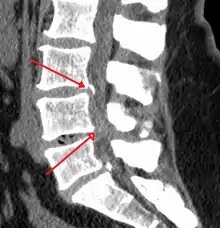

The diagnosis of spinal stenosis involves a complete evaluation of the spine. The process usually begins with a medical history and physical examination. X-ray and MRI scans are typically used to determine the extent and location of the nerve compression.

MRI

Myelography